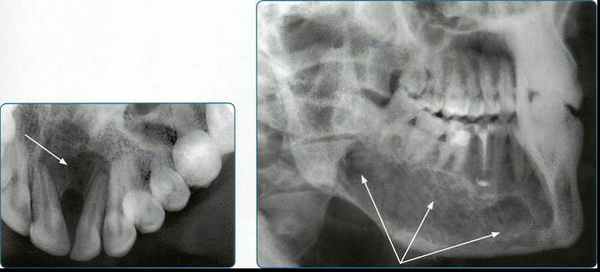

Рентгенограммы вприкус выполняют в тех случаях, когда невозможно сделать внутриротовые контактные снимки (повышенный рвотный рефлекс, тризм, у детей), при необходимости исследования больших отделов альвеолярного отростка (на протяжении 4 зубов и более) и твердого неба, для оценки состояния щечной и язычной кортикальных пластинок нижней челюсти и дна полости рта.

Стандартный конверт с пленкой вводят в полость рта и удерживают сомкнутыми зубами. Рентгенограммы вприкус используют для исследования всех зубов верхней челюсти и передних нижних зубов.

Также окклюзионная рентгенография применяется и для получения изображения дна полости рта при подозрении на конкременты поднижнечелюстной и подъязычной слюнных желез, для получения изображения челюстей в аксиальной проекции. Она позволяет уточнять ход линии перелома в пределах зубного ряда, расположение костных осколков, состояние наружной и внутренней кортикальных пластинок при кистах и новообразованиях, выявлять реакцию надкостницы